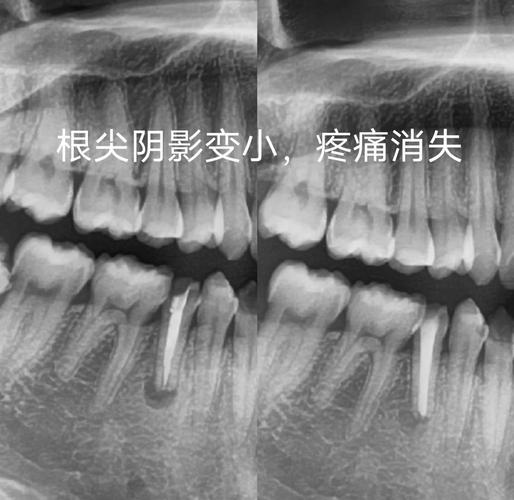

若根管治疗完毕后牙齿仍旧疼痛不已,或缺牙根发生炎症状况,先别着急去拔牙。可思索做根管再次治疗,借由更精细入微的显微技术去除残留的感染源头。倘若根尖发炎程度严重,也能够做根尖切除手术,将病灶直接予以处理。唯有当这些办法皆无成效,牙体组织着实无法修复的时候,才会迈向拔牙以及种牙那一步。优先保障自身牙齿,始终是首要原则。